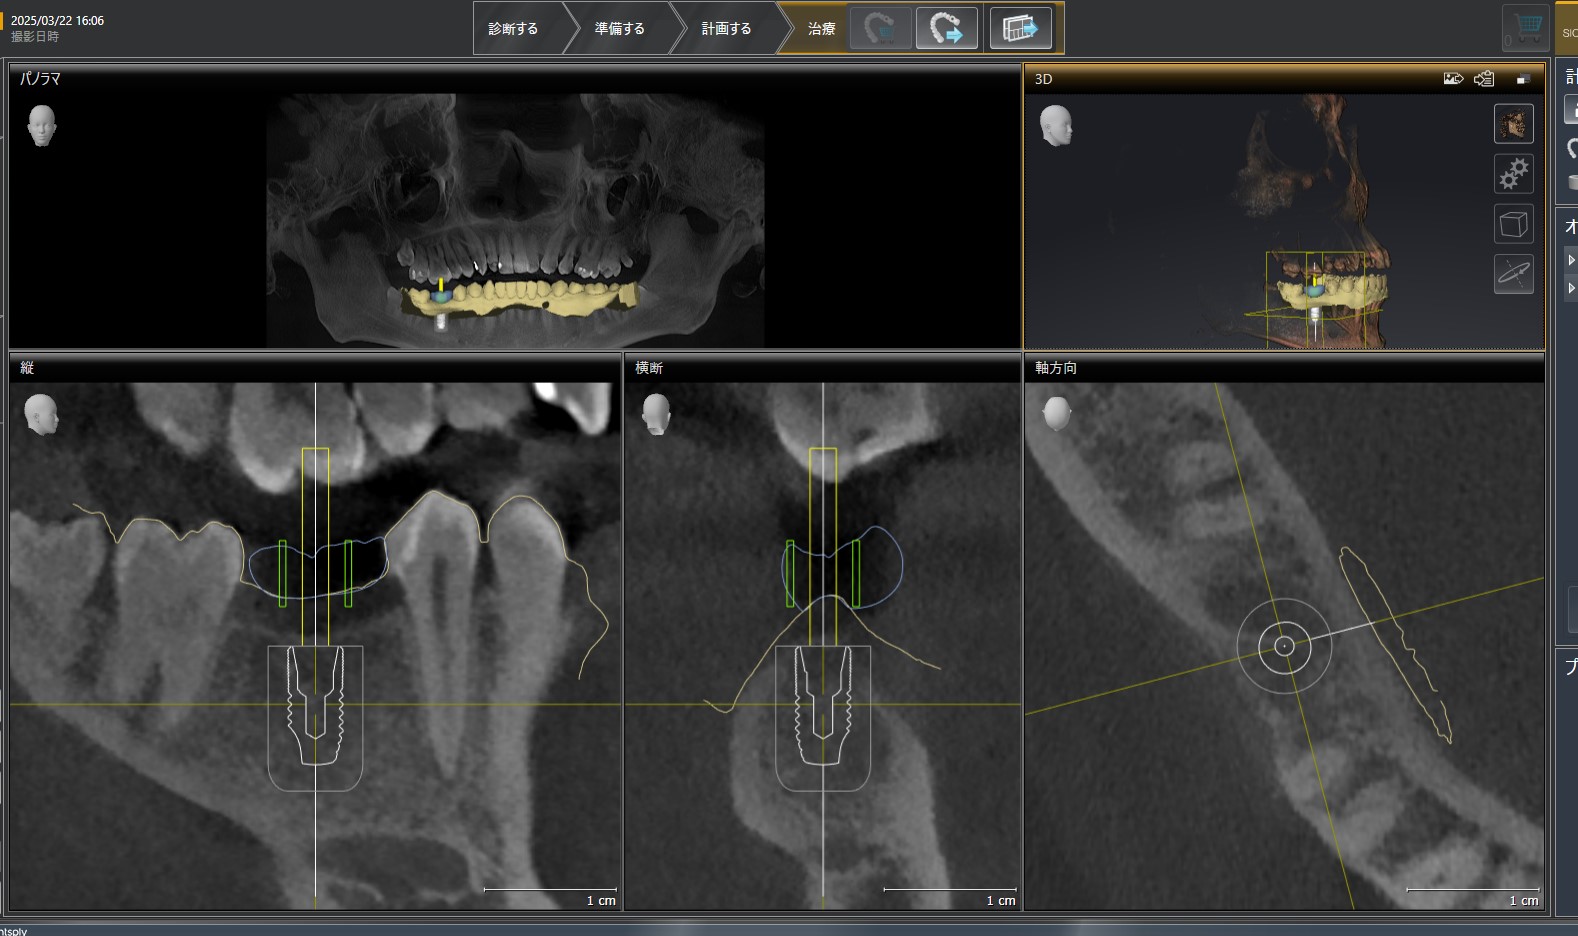

シュミレーション画像

CT画像